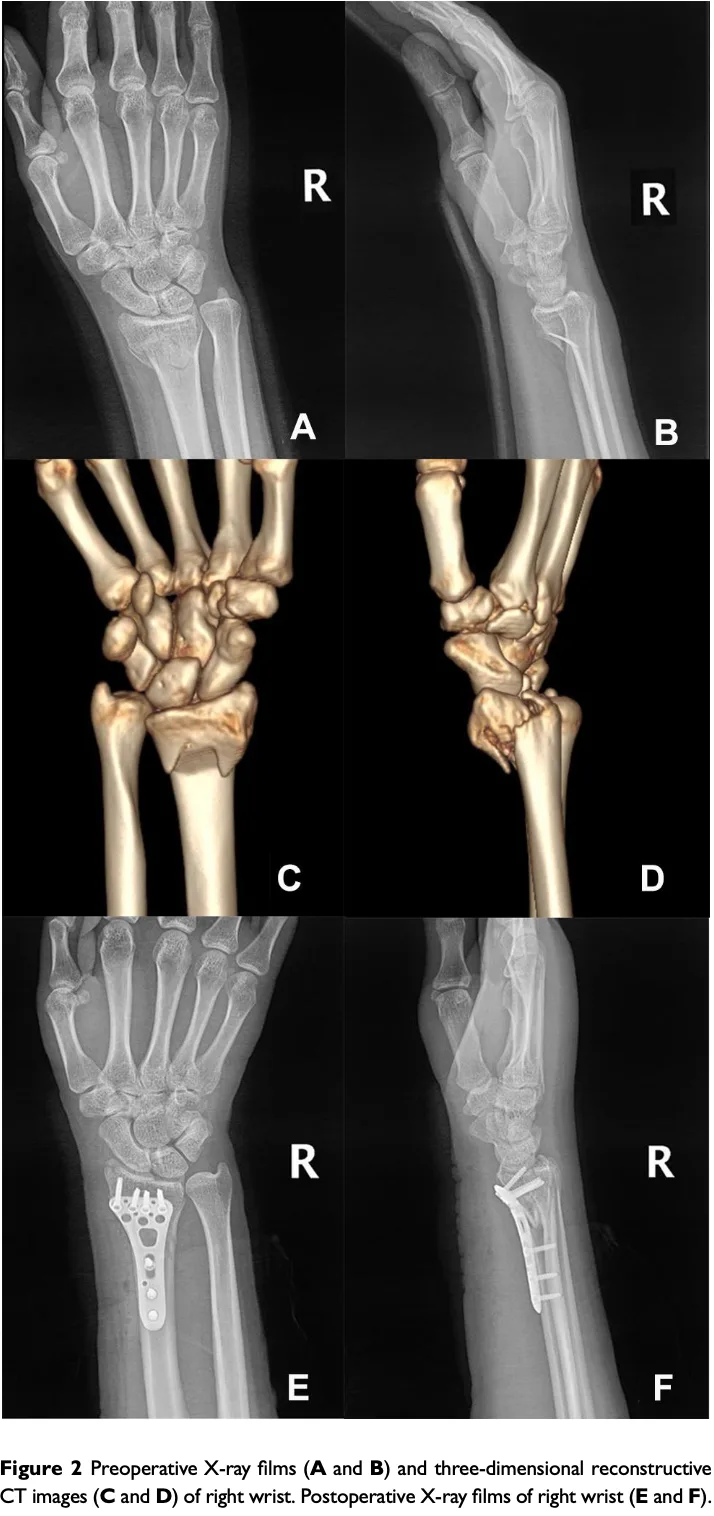

先輩医師のクリニックから, 橈骨遠位端骨折の前期高齢の患者さんが紹介で受診されました. 1週間前に転倒したとのこと. 持参されたX線を見ると, 掌側バートン(Barton)骨折でした.

バートン骨折のうち, 骨片が背側の場合は, 単にBarton骨折(または背側Barton骨折), 骨片が手のひら側の場合は, 掌側Barton骨折(または逆Barton骨折)と呼ばれます.

今回の患者さんは関節面の掌側に骨片が転位している掌側Barton骨折で, 転位もあったため手術が必要と判断. 術前検査を進め, 来週の手術枠を調整しました.